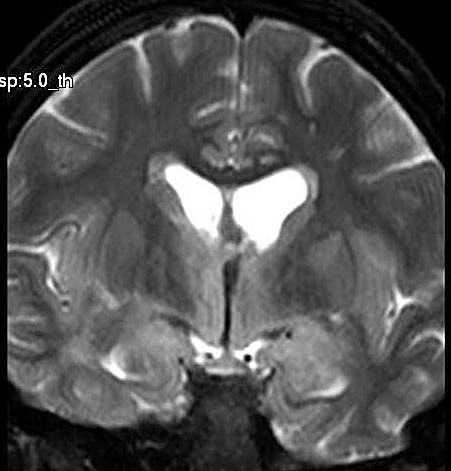

| Fem. 17a. |

| Nódulo sólido homogêneo preenchendo o III ventrículo, com limites precisos, com hipossinal em T1 e hipersinal em T2 e FLAIR, que se impregna por contraste paramagnético. Lesão menor implantada no assoalho do IV ventrículo provavelmente representa disseminação por via liquórica. |

| CORTES CORONAIS, T2 | ||

| F. 17a. Tumor teratóide rabdóide atípico de III ventrículo. RM | HE | VIM, GFAP | HHF35, desmina, 1A4 | AE1AE3, EMA |